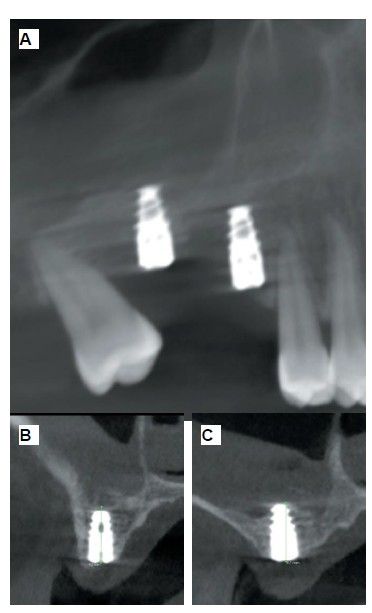

The medical history revealed no relevant medical or surgical antecedents, no known drug allergies, and no harmful habits. Intraoral examination revealed the absence of 1.6 and 1.7, and the presence of 1.8 and 4.8 (Figure 1). Radiographic examination using cone beam computed tomography (CBCT) revealed a residual height of 5.0 mm at 1.6, where an implant could be placed simultaneously, and 2.6 mm in the region of 1.7, making simultaneous implant placement with the lateral approach sinus elevation difficult (Figure 2).

Six months after the maxillary sinus elevation surgery, re-entry was performed for the placement of implants. A 3 x 7mm bone tissue biopsy was obtained using a trephine, and histomorphometric analysis was requested, revealing 30.56% vital bone (Figure 7). After the biopsy sample was taken, two bone level Naturactis implants from ETK® (ETK Implants S.L, Sant Boi de Llobregat, Spain) were placed with an insertion torque of 35 Ncm, and their correct positioning was confirmed in the immediate postoperative period by means of a periapical radiograph (Figure 8). Six months after the placement of the implants, the patient was able to attend for the second stage to place healing abutments. A verification CBCT was performed to assess the final bone height, revealing an increase of 4.2 mm in the region of 1.6 and 6.1 mm in the region of 1.7 (Figure 9).